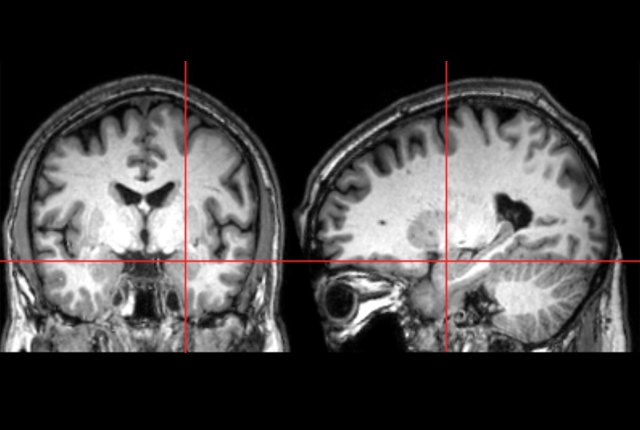

Researchers have long known the amygdala is significantly larger in school-age children diagnosed with autism, but it was unknown precisely when that enlargement occurs. Now, for the first time, researchers from the Infant Brain Imaging Study (IBIS) Network, which includes the University of Washington, used magnetic resonance imaging (MRI) to demonstrate that the amygdala grows too rapidly in infancy. Overgrowth begins between 6 and 12 months of age, before the characteristics of autism fully emerge, potentially enabling the earliest identification of this condition.

The new study, published March 25 in the American Journal of Psychiatry, is the first to document amygdala overgrowth before autism appears clinically. The research was conducted through the IBIS Network, a consortium of 10 universities in the United States and Canada.

“We also found that the rate of amygdala overgrowth in the first year is linked to the child’s social deficits at age two,” said first author Mark Shen, assistant professor of psychiatry and neuroscience at the University of North Carolina Chapel Hill and faculty of the Carolina Institute for Developmental Disabilities. “The faster the amygdala grew in infancy, the more social difficulties the child showed when diagnosed with autism a year later.”

Earlier studies by the IBIS team and others revealed that even though the social deficits that are a hallmark of autism are not present at 6 months of age, infants who go on to develop autism have altered attention to visual stimuli in their surroundings in the first year of life. The authors hypothesize that these early alterations with processing visual and sensory information may place increased stress on the amygdala, leading to its overgrowth.